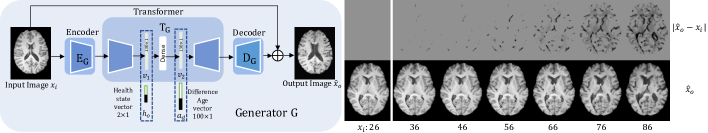

The ability to predict the future state of an individual can be of great benefit for longitudinal studies [72]. However, such learned phenomenological predictive models need to capture anatomical and physiological changes due to ageing and separate the factors that influence future state. Recently, deep generative models have been used to simulate and predict future degeneration of a human brain using existing scans [49, 48, 47]. However, current methods require considerable amount of longitudinal data to sufficiently approximate an auto-regressive model. Here, we propose a new conditional adversarial training procedure that does not require longitudinal data to train. Our approach (shown in Fig. 1) synthesises images of aged brains for a desired age and health state.

Fig. 1: Left: The input is a brain image xisubscript𝑥𝑖x_{i}, and the network synthesises an aged brain image x^osubscript^𝑥𝑜\hat{x}_{o} from xisubscript𝑥𝑖x_{i}, conditioned on the target health state vector hosubscript𝑜h_{o} and target age difference ad=aoaisubscript𝑎𝑑subscript𝑎𝑜subscript𝑎𝑖a_{d}=a_{o}-a_{i} between input aisubscript𝑎𝑖a_{i} and target aosubscript𝑎𝑜a_{o} ages, respectively. Right: For an image xisubscript𝑥𝑖x_{i} of a 26 year old subject, bottom row shows outputs x^osubscript^𝑥𝑜\hat{x}_{o} given different target age. The top row shows the corresponding image differences |x^oxi|subscript^𝑥𝑜subscript𝑥𝑖|\hat{x}_{o}-x_{i}| to highlight progressive changes.

In this paper, we build the foundations of a model that can be trained without longitudinal data. A simplified schematic of our model is shown in Fig. 1 along with example results. Given a brain image, our model produces a brain of the same subject at target age. The input image is first encoded into a latent space, which is modulated by two vectors representing target age difference and health state (AD status in this paper), respectively. The conditioned latent space is finally decoded to an output image, i.e. the synthetically aged image.